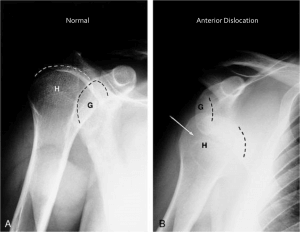

Until 6 weeks after an open rotator cuff repair, even gentle isometrics are not recommended.- Following anterior dislocation of shoulder joint: extension beyond 0 degrees is contraindicated. The forearm is moved from in front of the trunk (maximal internal rotation) to 0 or possibly 10 to 15 degrees external rotation. Also, anterior glide is contraindicated although external rotation is important for a functional elevation of the arm. The shoulder is immobilized in a sling or splint in adduction and internal rotation. The forearm is rested across the abdomen with the arm slightly anterior to the midline of the body.